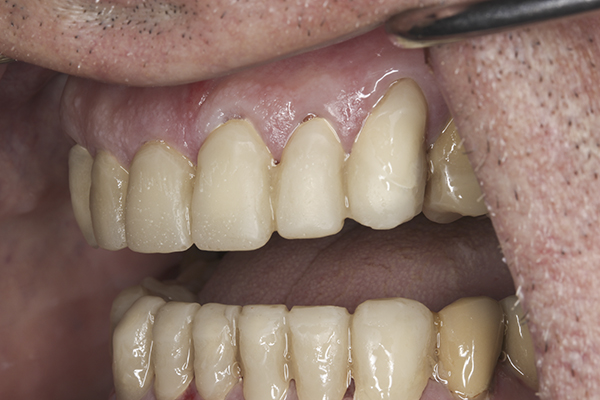

(34.) Postoperative left lateral, open view.

Figure 34

(36.) Postoperative anterior, closed view. Note the position of the upper and lower canines to provide canine guidance.

Figure 36

Based on examination of the mounted models, it was decided to treat the patient in centric relation and an additive equilibration approach was used to idealize the planes of occlusion. On the articulator, the patient’s first point of contact in centric relation was the starting point and an additive equilibration technique was implemented, building the teeth to meet ideally at the patient’s first point of contact. A diagnostic wax-up was completed on the mounted models to determine where the anterior and posterior teeth needed to be in space. A template from the wax-up was used to fabricate the anterior provisional restorations. The anterior teeth were restored with full-coverage restorations, creating ideal stops between the lower incisal edges and upper cingulums. The maxillary incisal edges were placed to provide proper phonetics and an acceptable esthetic outcome, while still working within the envelope of function. All of these parameters are worked out in the provisionals prior to moving forward with definitive restorations. With the anterior provisionals in place, posterior composite tops were bonded to his existing dentition, creating ideal centric stops on the posterior teeth. The anterior and canine guidance was developed, resulting in immediate separation of the posterior teeth during all excursive movements (Figure 17 through Figure 28). Once the author and patient were happy with the function, esthetics, phonetics, and comfort of the provisionals, an impression of the approved provisionals was taken and sent to the laboratory to use as a guide in the fabrication of the final anterior crowns. With the final restorations delivered, the patient was extremely happy with his new smile. Most importantly, proper anterior and canine guidance in harmony with his envelope of function was achieved, which resulted in comfortable function and immediate separation of the posterior teeth during protrusive and lateral excursions (Figure 29 through Figure 42).